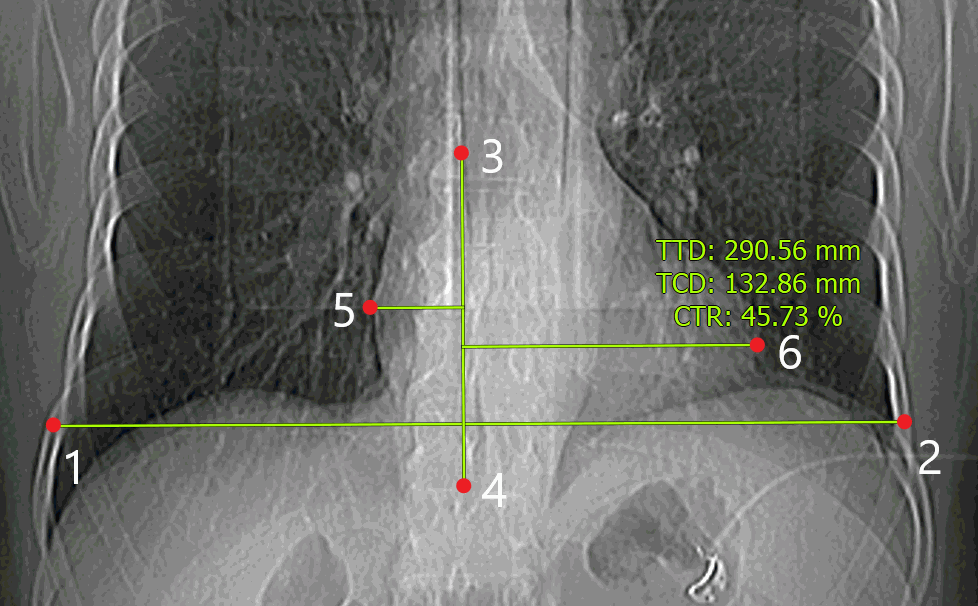

To measure the cardiothoracic ratio, proceed as follows:

1. Activate the Cardiothoracic ratio PIC tool from the toolbar by clicking the left/right/middle mouse button. To continue work with this tool, use the button with which the tool was activated. To learn more about tool control, see Section 1.14.

2. Measure the thoracic diameter by marking points on the inside of the ninth rib (points 1 and 2 in Fig. 2.32).

3. Build the vertebral column axis (points 3 and 4 in Fig. 2.32).

4. Measure the transverse cardiac diameter by marking the outermost points of the left and the right contours (points 5 and 6 in Fig. 2.32).

5. To cancel an incomplete measurement, press Esc.

Next to the measurement, you can see the following results:

• transverse thoracic diameter (TTD)) in millimeters;

• transverse cardiac diameter (TCD) in millimeters;

• cardiothoracic ratio (CTR) as a percentage.

This tool is also available from the image context menu and from the Image main menu item. Activation is only possible with the left mouse button.